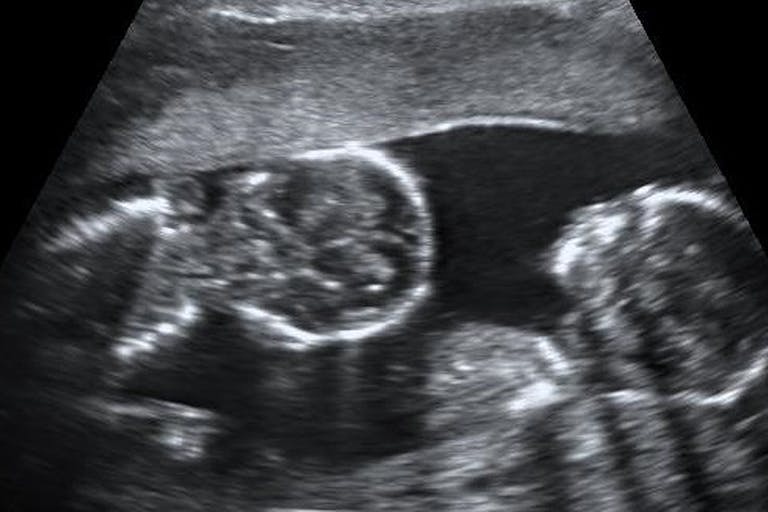

Twins saved from abortion after mother sees her babies on ultrasound

It was inside the van that Valerie received her second surprise — the sonogram showed she was carrying twins!

Though overwhelmed, she was also encouraged by the number of resources available through the pregnancy center with the van and other programs in her community. It was then that she decided to give birth to her two babies. She later wrote,

“I thank God that He led me to this van outside of the abortion clinic and for the lady who offered me a sonogram and other support. Because of her, I was able to see my surprise twins and chose to continue with my pregnancy. I recommend my friends and anyone I know who is going through a rough time to go to Englewood for help if they are pregnant and have no one to go to.”